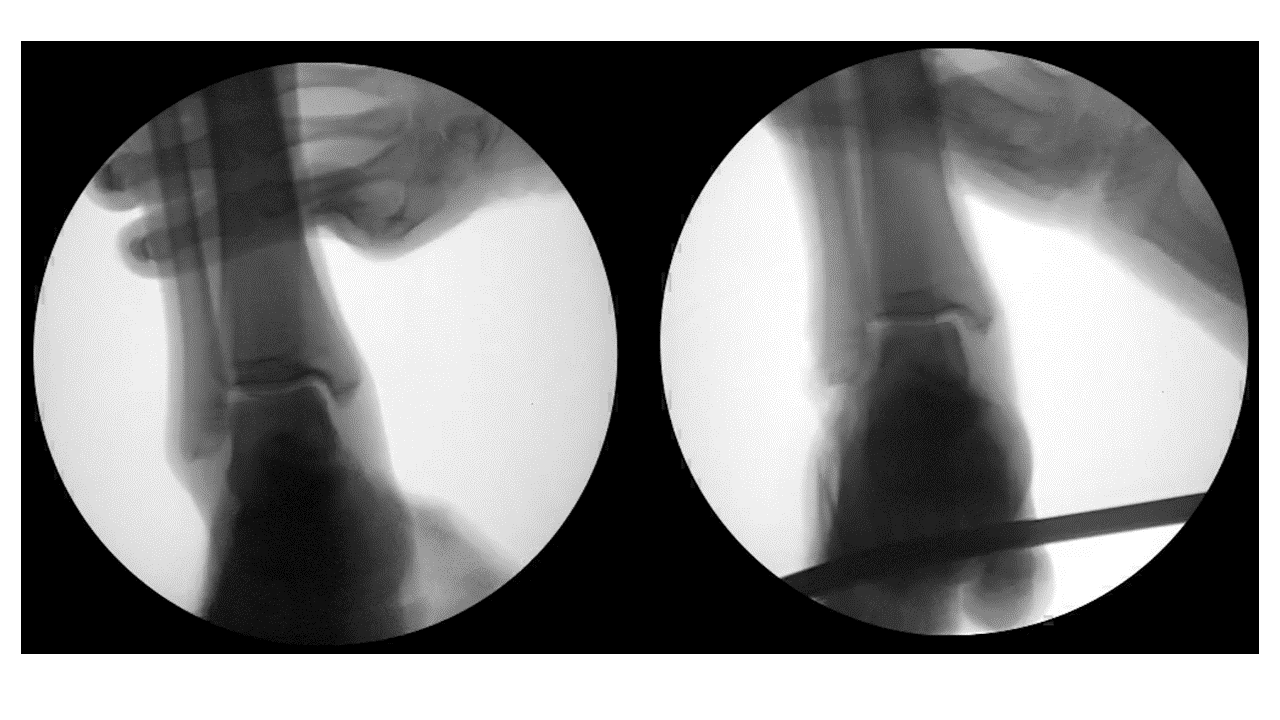

This animation is courtesy of Taggart Gauvain, MD.